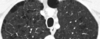

18

A

Patrón intersticial reticular

19

20

21